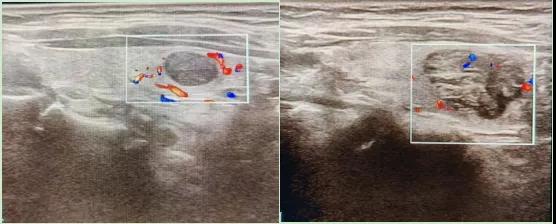

二、彩超如何“揪出”甲狀腺瘤?

彩超是一種無創(chuàng)、無輻射的檢查手段,被譽(yù)為甲狀腺的“高清攝像頭”。它的原理是:

超聲波探測:通過發(fā)射高頻聲波,生成甲狀腺的實(shí)時(shí)圖像。

彩色血流顯示:用紅藍(lán)色標(biāo)記血流信號,區(qū)分腫瘤的供血情況。

醫(yī)生會通過以下特征判斷腫瘤性質(zhì):

1.形態(tài):良性多呈圓形,邊界清晰;惡性可能不規(guī)則、邊緣模糊。

2.回聲:低回聲結(jié)節(jié)風(fēng)險(xiǎn)較高(像“烏云”一樣暗)。

3.鈣化:細(xì)小砂礫樣鈣化提示惡性可能。

4.血流信號:惡性結(jié)節(jié)常有豐富紊亂的血流。